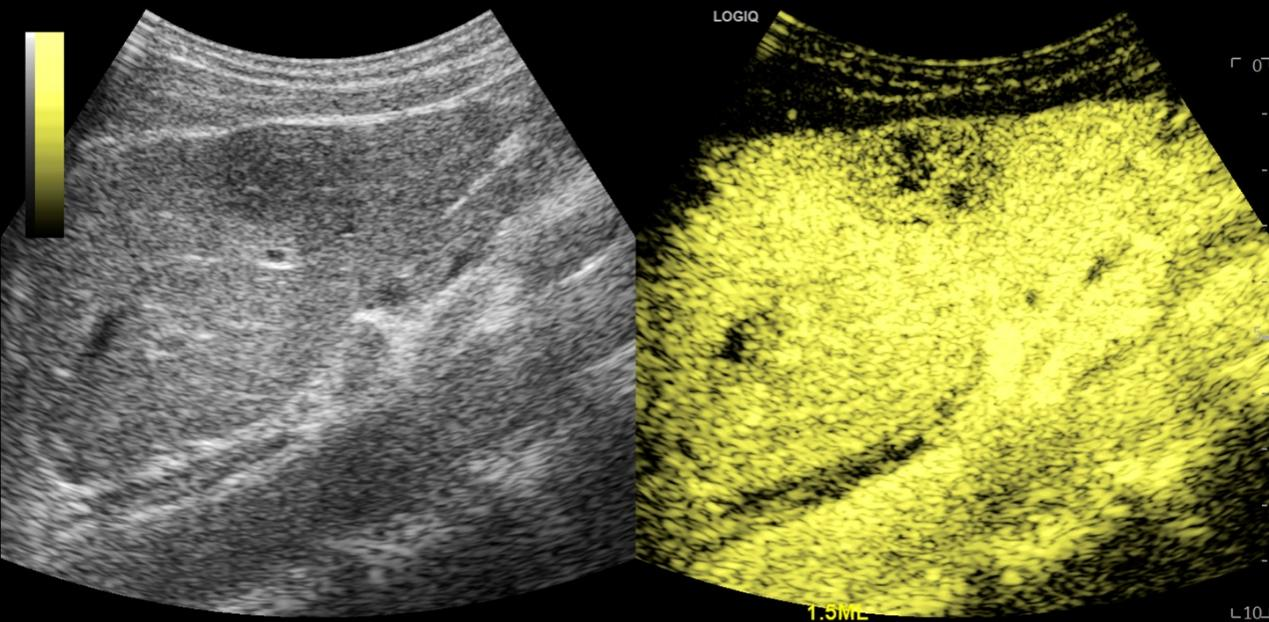

科室特色:超声造影检查

图3 肝脏肿瘤超声造影图像

超声造影是近几年来超声领域蓬勃发展的诊断新技术之一,在欧洲、美国和日本,对其临床应用价值做了大量的研究,证实超声造影的诊断能力不逊于CT和MRI,并为其规范使用制定了应用指南。

我院本部(复旦中山医院超声科)是国内最早开展肝脏疾病超声造影研究和应用的部门之一,近十年来做了大量的肝脏超声造影的临床研究,同时在胆胰肾、甲状腺和乳腺等方面也做了一定的研究,积累了丰富的临床经验,在国内外的学术期刊上发表近百篇相关论文,申请获得数十个国家级及上海市科研基金项目,成果获得国家级、上海市等多项科技奖。超声造影诊断肝脏局灶性病变准确性高,其应用价值被临床医生肯定,已常规应用于临床以明确病情。